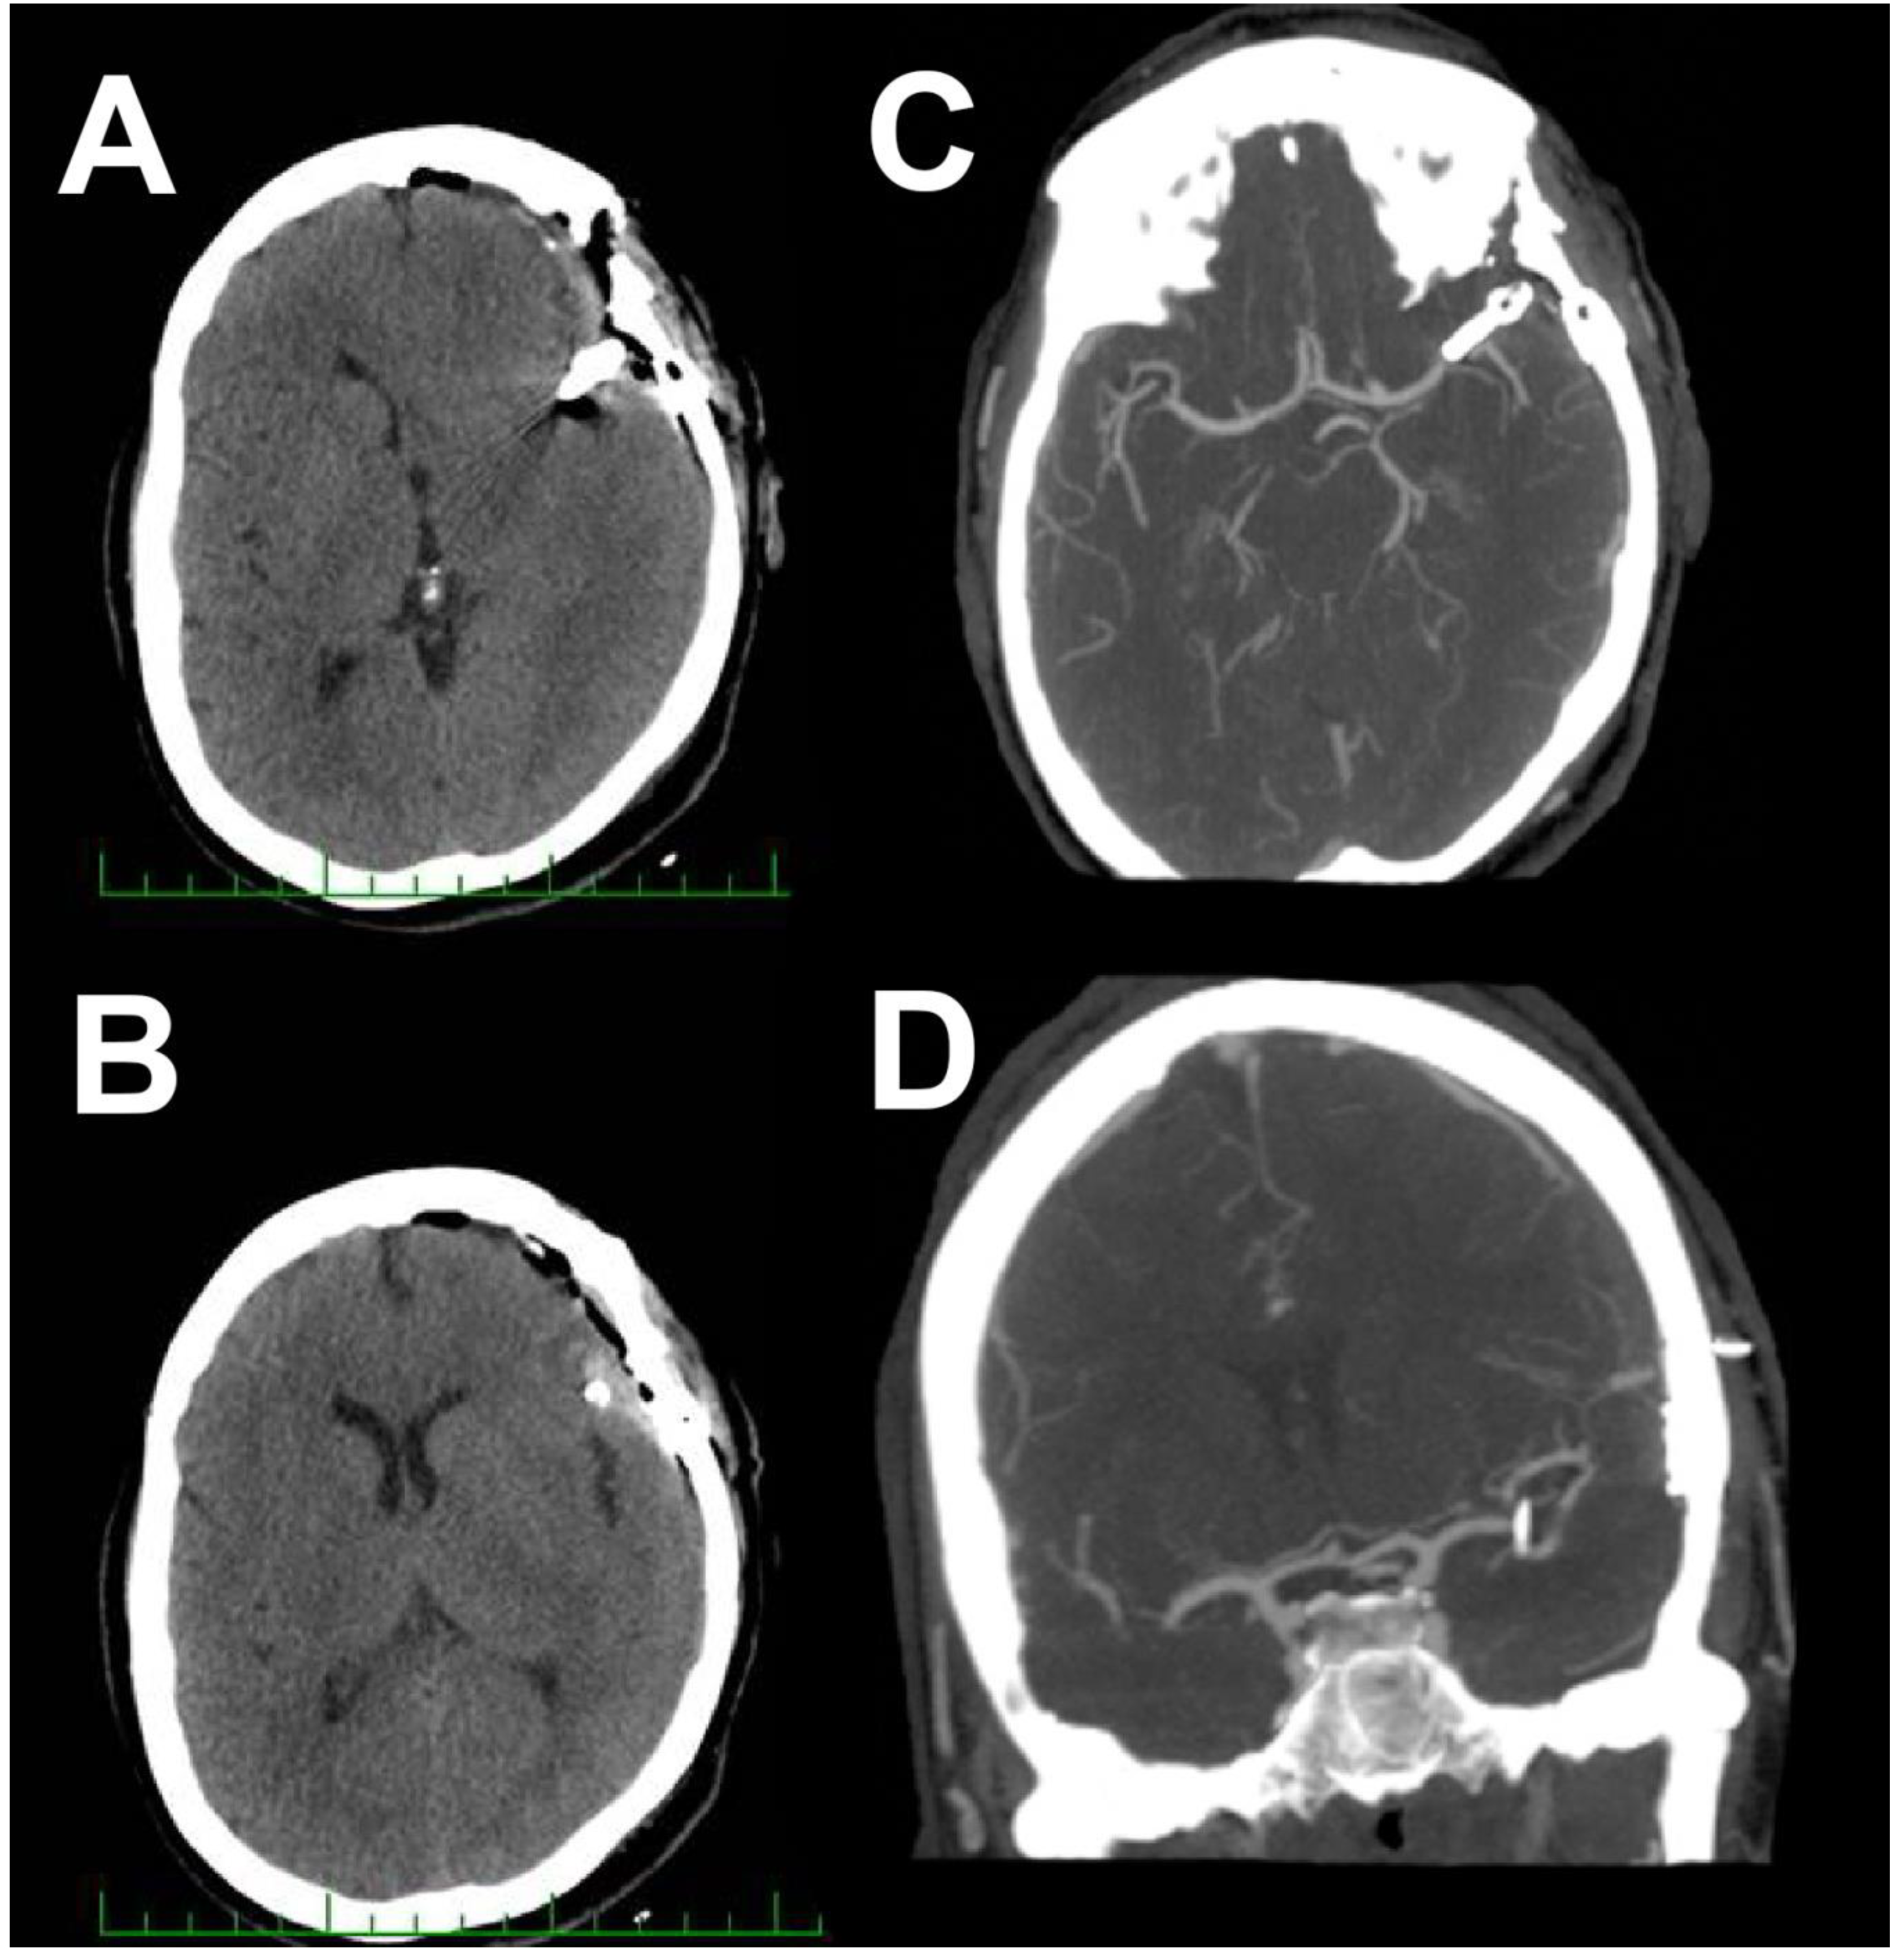

2. Case Report 1

3. Case Report 2